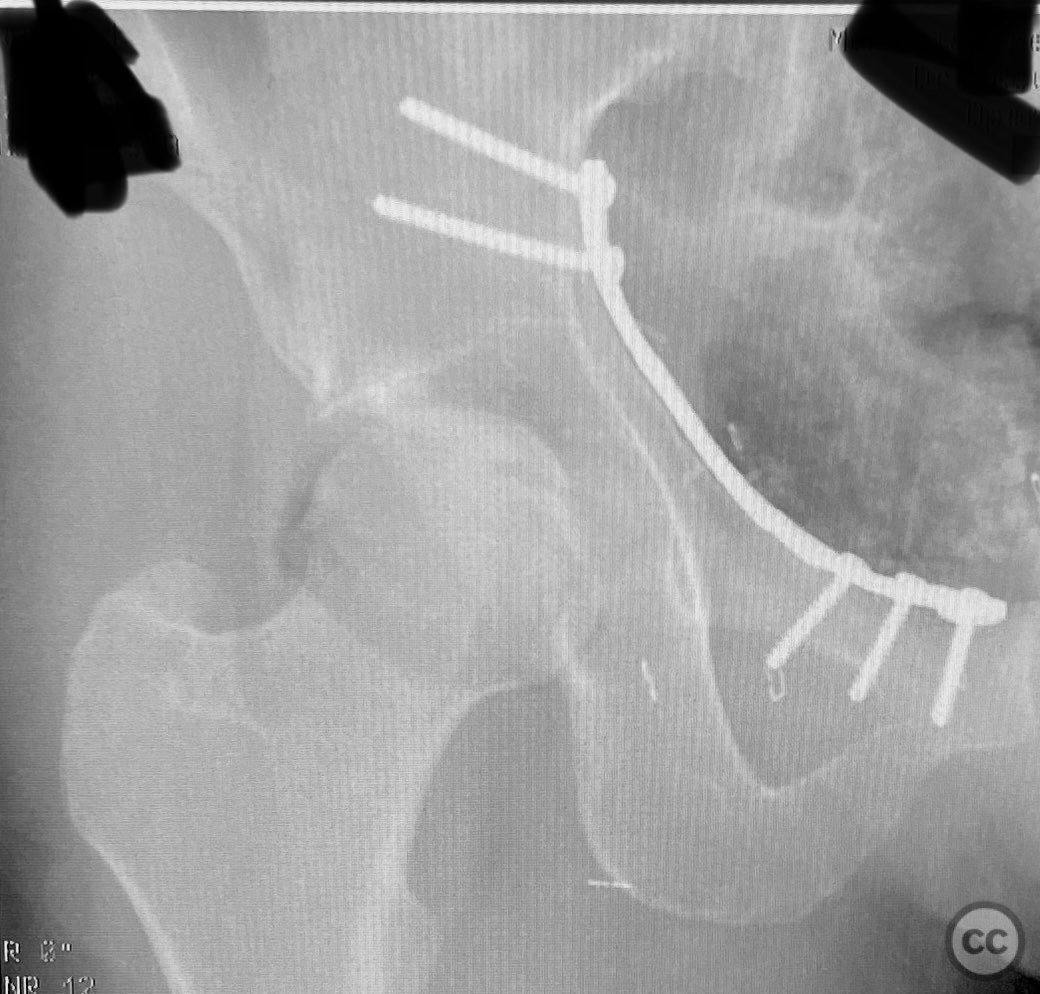

Clinical and radiological findings:  The patient sustained an acetabular fracture with a rare posterior medial dome impaction fragment, as demonstrated on AP pelvic radiographs obtained in skeletal traction. Surface renderings and axial CT images revealed multiple incomplete fracture lines, including a rhomboid-shaped cortical fragment adjacent and proximal to the anterior column/wall fragment. Coronal and sagittal reconstructions further delineated the impacted articular fragment and its relationship to the surrounding acetabular dome. The fracture pattern is classified as AO/OTA 62B3 (associated both-column fracture with dome impaction).